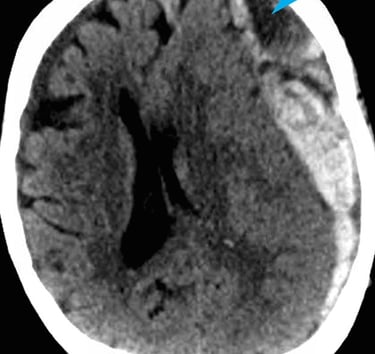

Hidrocefalia

Diagnóstico y manejo quirúrgico de la hidrocefalia.